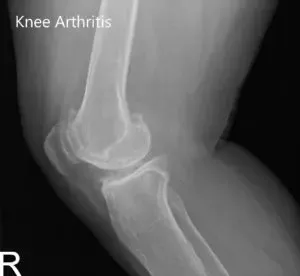

Imaging revealed severed tricompartmental osteoarthritis of the bilateral knee (right greater than left) with osteophytes and medial joint space reduction.

Preoperative X-ray of the right knee showing AP and lateral views